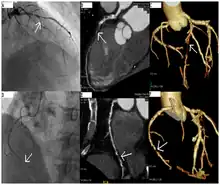

CT angiography can act as a less invasive alternative to Catheter angiography. Instead of a catheter being inserted into a vein or artery, CT angiography involves only the injection of a CT-visible dye into the arm or hand via an IV line. CT angiography lowers the risk of arterial perforation and catheter site infection. It provides 3D images that can be studied on computer, and also allows measurement of heart ventricle size. Infarct area and arterial calcium can also be observed (however those require a somewhat higher radiation exposure). That said, one advantage retained by Catheter angiography is the ability of the physician to perform procedure such as balloon angioplasty or insertion of a stent to improve blood flow to the artery.[7]